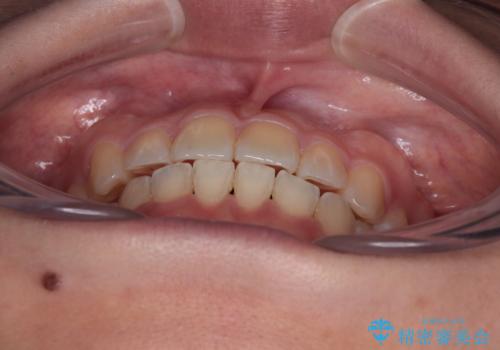

八重歯を治す 非抜歯のワイヤー矯正治療

- 左右の八重歯を気にして来院された患者様です。

舌の突出癖により上下前歯が開咬となりましたが、舌のトレーニングと顎間ゴムの使用により、元々の被蓋関係に改善することができました。

アンカースクリューを用いて、出っ歯仕上がりを回避し、正中位置も改善することができました。